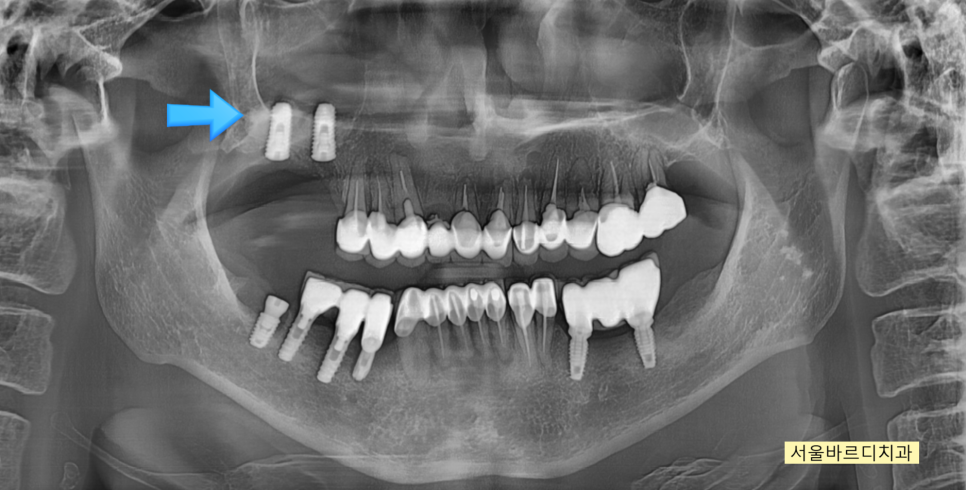

230908

같은 날 위아래 임플란트를 동시에 진행하였습니다.

윗니 어금니의 경우 뼈이식을 동반하였지만

뼈가 많이 부족하여

임플란트를 잇몸 안에 묻어두고 수술을 마무리하였습니다.

추후 한번 더 잇몸을 열어야하는 2차 수술이 필요하지만

임플란트가 외부 음식물과 같이 외부 요인으로 인해

감염 되지 않는다는 장점도 있습니다.

231226

수술 후 3개월 뒤 모습입니다.

임플란트 주변으로 뼈가 둘러싼 모습이 확인 된 후

잇몸을 여는 수술을 진행하였습니다 .